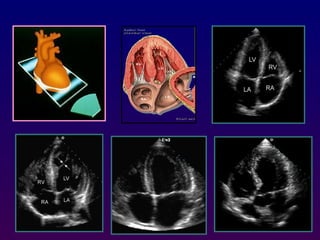

Each immage is determined by:

-The transducer position (parasternal, apical, subcostal,

suprasternal) Transducer position is altered by placing

the transducer at various locations on the thorax

-The tomographic view (long axis, short axis, 4- chamber,

5 chamber(.

which is often manipulated by a combination of angulation

and rotation of the transducer from the same position.